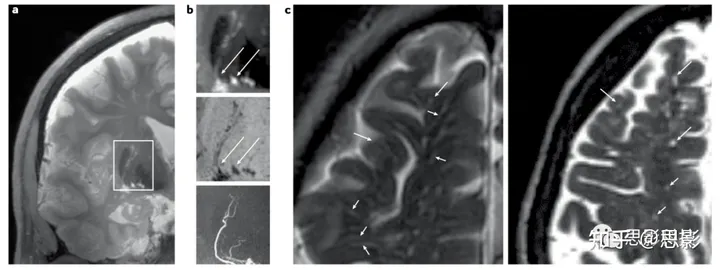

在年轻的大脑中,MRI上通常可以看到一两个小的血管周围间隙,但随着年龄的增长,通常会出现更多的可见间隙。无论数量如何,血管周围间隙通常出现在特定的大脑区域(图1):基底节(透镜状核,内外囊)紧挨着基底穿透物质的上方,那里它们通常可以看到与脑池CSF相连(图2);半卵圆中心,从白质外部向侧脑室方向向心性运行,包括在单基因SVDs(如脑自主性显性动脉病伴皮质下梗死和白质脑病(CADASIL))的前颞叶;海马;以及中脑,脑桥,有时在小脑白质中。

图2 | 人体活体高场和常规MRI的血管周围间隙。

a | 基底节穿透性动脉和血管周围间隙的冠状高场(7-T)T2加权MRI扫描。矩形表示在部分b中可视化的区域。b | T2加权MRI(顶部)和T1加权MRI(中部)显示与磁共振血管造影可见的动脉相对应的血管周围间隙(底部)。血管周围间隙的下端扩大与基底脑脊液相连(箭头)。c | 两个不同患者的额叶1.5-T T2加权MRI图像。可见接近皮质的血管周围间隙(短箭头),向皮质内缘更加扩张(长箭头),但在皮质中看不到它们。

血管周围间隙结构在区域解剖上的差异也为单独的区域定量提供了理由。高场(7-T)MRI显示基底节血管周围间隙直接与基底蛛网膜池相通(图2),而半卵圆中心的血管周围间隙则围绕从凸面皮质进入大脑的血管,看起来像是从皮质下几毫米处开始的。在人类尸体组织研究中,紧挨皮质下开始的血管周围间隙的外观类似于在较低场强MRI上观察到的情况(图3);在组织学和双光子成像实验中的啮齿动物模型中也是如此,表明MRI和组织病理学发现是相符的。